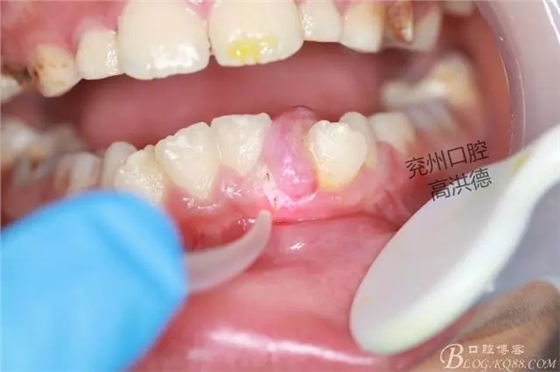

繼續(xù)切除

切除物

口內(nèi)觀

此病例以手術(shù)為主,傳統(tǒng)術(shù)式拔除患區(qū)牙齒去除部分牙槽骨防止復(fù)發(fā),往往病人不能接受,而容易復(fù)發(fā)。保留牙齒,使用激光手術(shù)切除腫物,可對牙周膜和牙槽骨有一定燒灼作用,減輕了患者術(shù)后復(fù)發(fā)的幾率。術(shù)中出血少,安全無痛,術(shù)后不影響進(jìn)食,臨床中值得大力推廣使用。